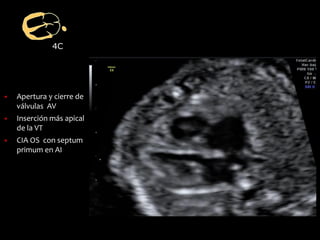

4C

▪ Apertura y cierre de

válvulas AV

▪ Inserción más apical

de la VT

▪ CIA OS con septum

primum en AI